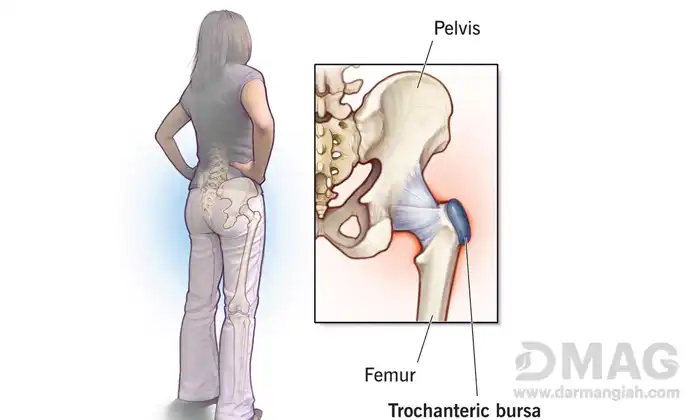

اکثر افراد در طول دوران زندگی خود معمولا دچار درد استخوان لگن می شوند در واقع درد لگن یکی از مشکلات مربوط به دستگاه اسکلتی – عضلانی است که معمولا از سن ۴۰ سالگی به بعد شیوع این عارضه بیشترمی شود.

عوامل متنوعی مانند افزایش سن، چاقی و اضافه وزن و از همه مهم تر ضربه و تصادفات در بروز این مشکل دخیل هستند که باعث می شوند این بیماری به طور ناگهانی و یا تدریجی ایجاد شود. اگر چه درد اصلی لگن مربوط به مفصل گوی و کاسه لگن است اما توجه داشته باشید دیگر اجزای ساختار لگن مانند کمر و ران ها نیز در بروز این عارضه نقشی اساسی دارند. بنابراین دلیل وقوع درد لگن هرچه باشد بهتر است سریعتر به فکر درمان و رفع آن باشید. در ادامه این مبحث به مواردی از مهم ترین دلیل وقوع درد لگن اشاره خواهیم کرد.

شکستگی و در رفتگی

یکی از شایع ترین علت های درد لگن در رفتگی و شکستگی به خصوص در افراد مسن است. این درد به سرعت و با شدت زیاد در ناحیه لگن بروز کرده و هر گونه تحرکی شدت آن را افزایش می دهد. شکستگی و در رفتگی لگن معمولا به دلیل پوکی استخوان، ضربه های شدید و زمین خوردگی ایجاد می شود. همچنین برخی بیماری ها مانند سرطان استخوان، مشکلات ژنتیکی و انواع تومورها و … نیز بافت تراکم استخوانی را کاهش داده و منجر به شکستگی لگن می شوند. قرص برای درد استخوان لگن در این موارد معمولا شامل استفاده از مسکن های قوی می شود.

آرتروز

آرتروز یک درد شایع لگنی در افراد میانسال است که معمولا با بالا رفتن سن و ساییدگی تدریجی غضروف ها بیشتر می شود. آرتروز لگن موجب کشیده شدن استخوان های لگن بر روی هم شده و در نتیجه درد و التهابات لگن را چندین برابر خواهد کرد. درد لگن ناشی از آرتروز با بی تحرکی نیز تشدید می شود و با شروع مجدد حرکت تا حدودی آرام شده اما بعد از مدتی فعالیت تشدید می شود.